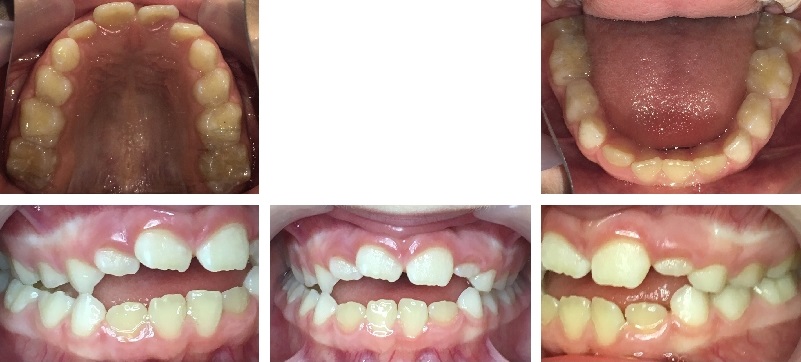

Before

After